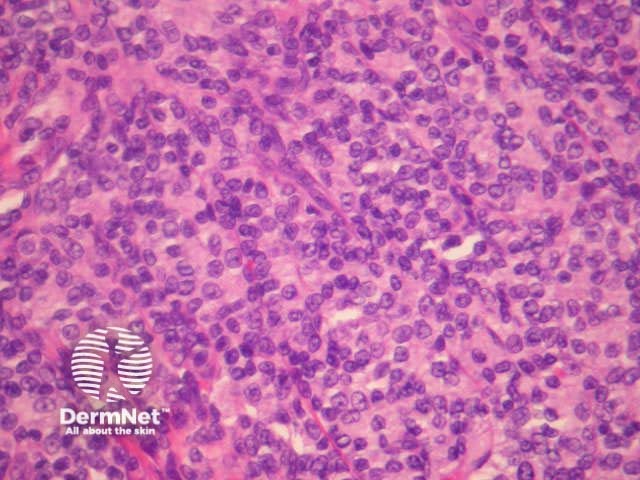

Histologically, indolent CD8+ lymphoid proliferations are characterised by a dense dermal infiltrate of non-epidermotropic, medium sized pleomorphic lymphocytes. These form a dense mass in the dermis and may involve subcutaneous tissues (figures 1-5).